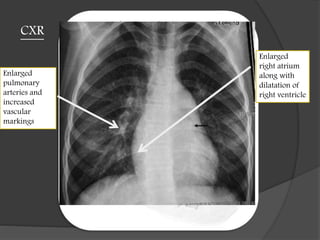

CXR

Enlarged

pulmonary

arteries and

increased

vascular

markings

right atrium

along with

dilatation of

right ventricle